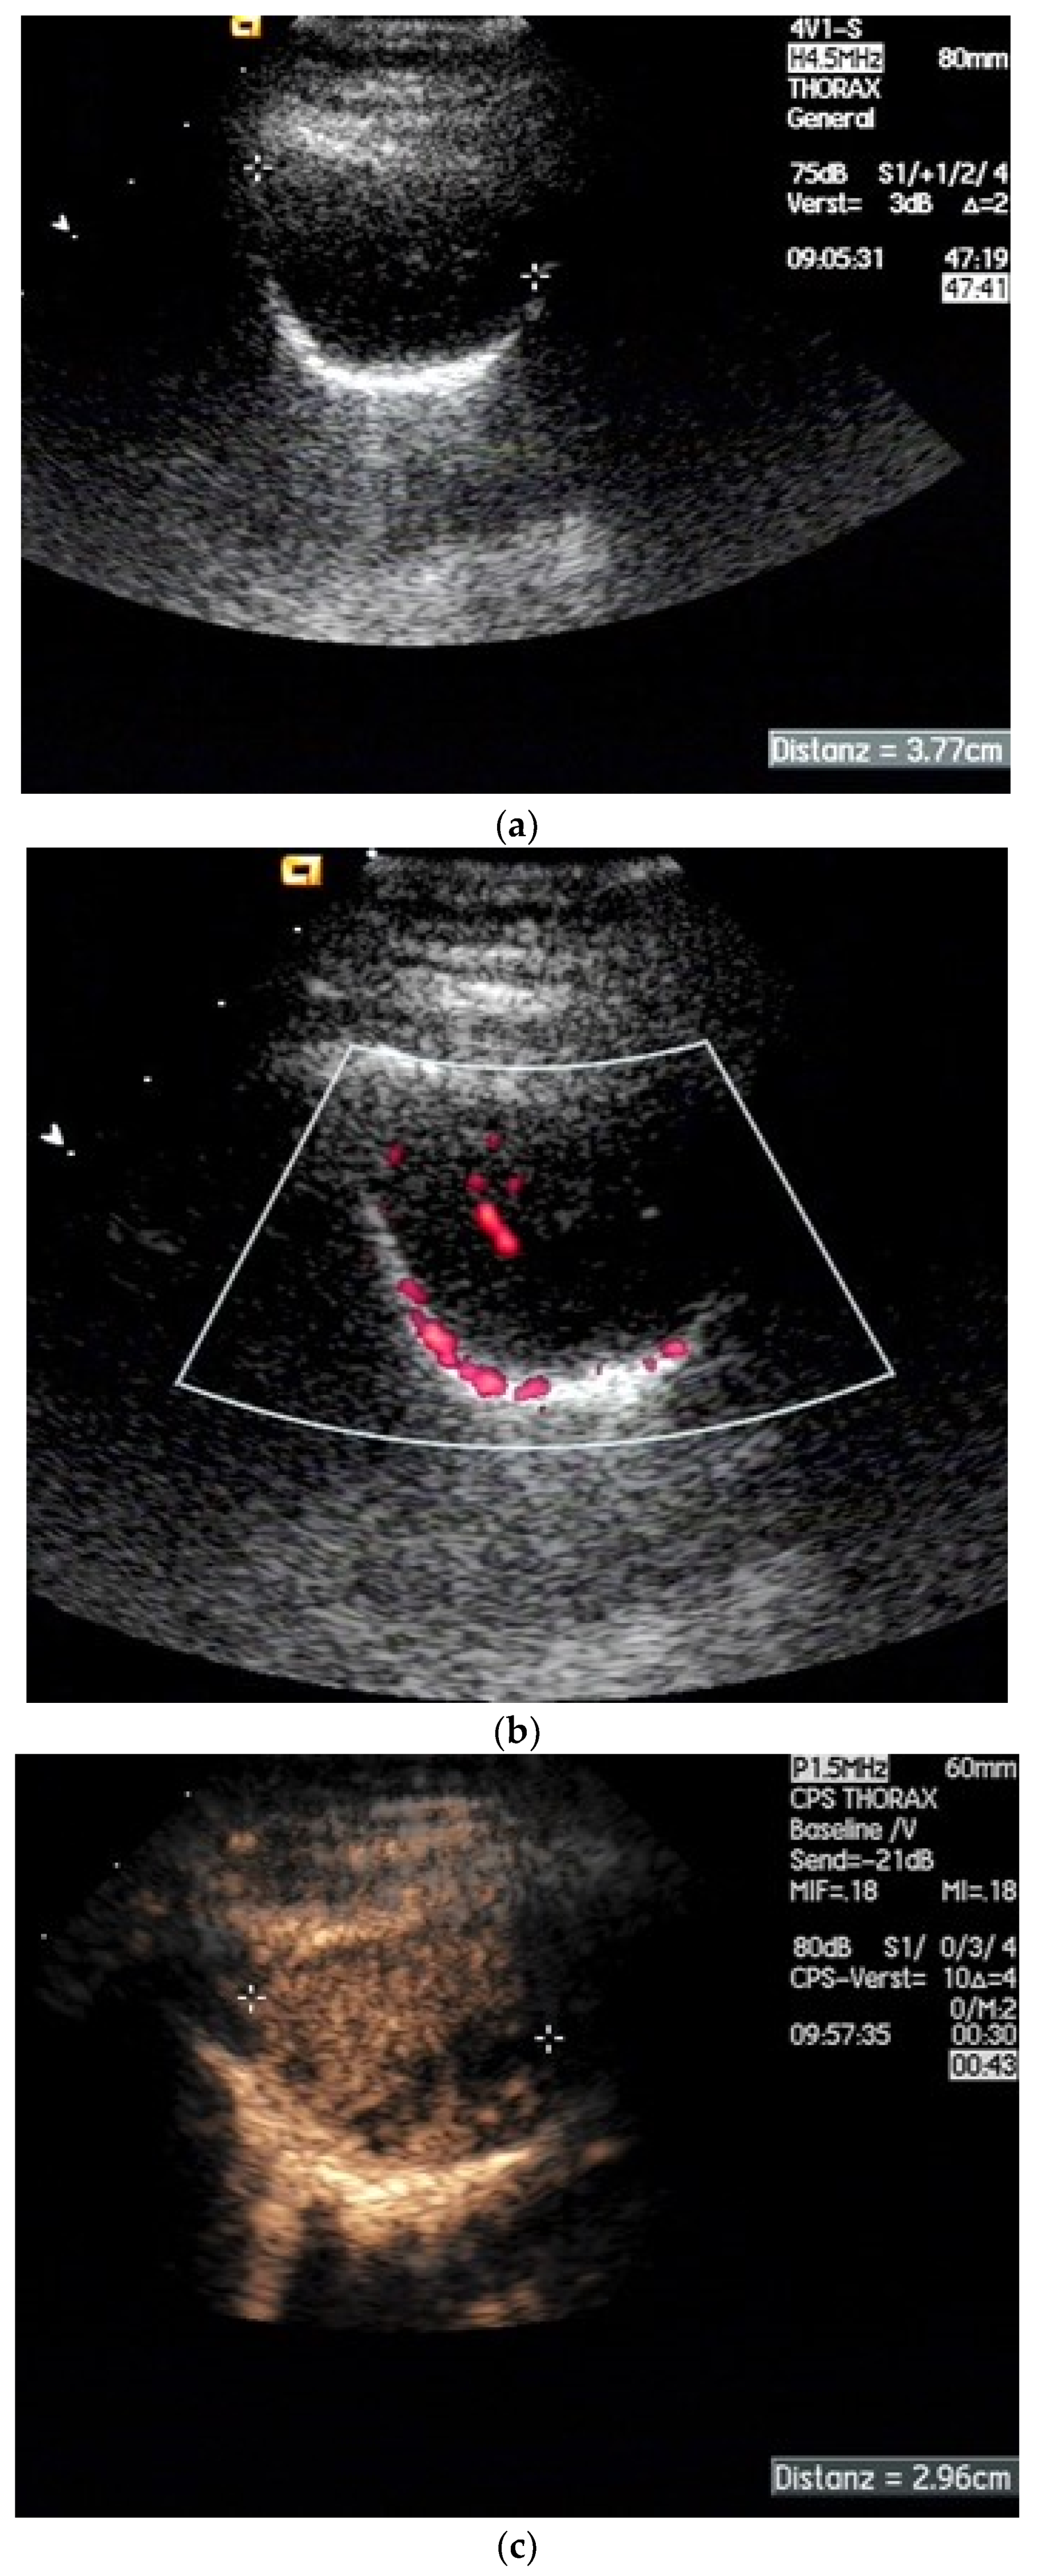

| Splenosis | Round, homogeneous lesions. Macrovessels on CDI are possible. Spleen-typical contrast behavior in CEUS with long-lasting contrast enhancement over several minutes. |